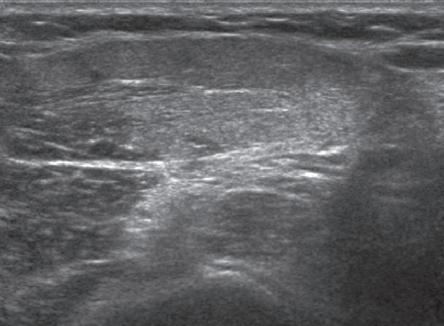

One should be familiar with several artifacts common to musculoskeletal ultrasound.5 One

such artifact is anisotropy 6 When a tendon is imaged perpendicular to the ultrasound beam, the characteristic hyperechoic fibrillar appearance is displayed. However, when the ultrasound beam is angled as little as 2 to 3 degrees relative to the long axis of such a structure, the normal hyperechoic appearance is lost; the tendon becomes more hypoechoic with increased insonation angle (Figs. 1.10 to 1.13). A tissue is anisotropic if its properties change when measured from different directions. This variation of ultrasound interaction with fibrillar tissues involves tendons and ligaments and, to a lesser extent, muscle. Because abnormal tendons and ligaments may also appear hypoechoic, it is important to focus on that segment of tendon or ligament that is perpendicular to the ultrasound beam, to exclude anisotropy. With a curved structure, such as the distal aspect of the supraspinatus tendon, the transducer is continually repositioned or angled to exclude anisotropy as the cause of a hypoechoic tendon segment (Fig. 1.11 and Video 1.3). Anisotropy is noted both in long axis and short axis of ligaments and tendons (Video 1.4), but it occurs when the sound beam is angled relative to the long axis of a structure (Fig. 1.12). Therefore, to correct for anisotropy, the transducer is angled along the long axis of the imaged tendon or ligament; when imaging a tendon in long axis, the transducer is angled as a heel-toe maneuver (see Fig. 1.3A and Video 1.5), whereas in short axis, the transducer is toggled (see Fig. 1.3B and Video 1.6). Anisotropy can be used to one’s advantage in identification of a hyperechoic tendon or ligament in close proximity to hyperechoic soft tissues, such as

FIGURE 1.11 Anisotropy. Ultrasound images of distal supraspinatus tendon in long axis (S) shows an area of hypoechoic anisotropy (curved arrow) (A), where the tendon fibers become oblique to the sound beam, which is eliminated (B) when the transducer is repositioned so that the tendon fibers are perpendicular to the sound beam. H, Humerus.